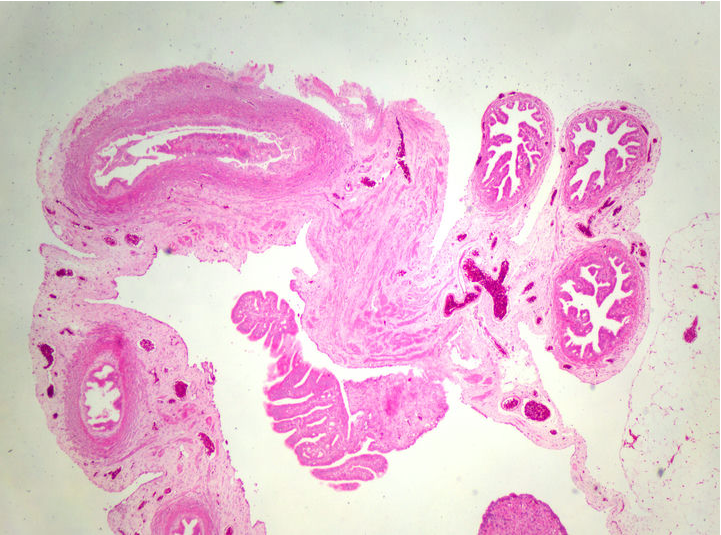

生物顯微鏡下的卵巢病理切片

病理切片是病理科醫(yī)生確診病癥的重要工具,觀察病理切片一般使用生物顯微鏡明場觀察,一款好的病理切片顯微鏡,不僅要求使用舒適,還要成像清晰。在生物顯微鏡ML31的觀察下,經(jīng)過HE染色的卵巢切片呈粉紅色,并呈現(xiàn)出豐富而復(fù)雜的細節(jié)。

卵巢,作為女性生殖系統(tǒng)的重要器官,負責產(chǎn)生卵子和分泌性激素。透過生物顯微鏡ML31,我們可以看到許多不同種類的細胞。其中較突出的是卵原細胞,這是卵巢中產(chǎn)生卵子的母細胞。在染色切片中,卵原細胞呈現(xiàn)出較大的體積和較深的染色,與其他細胞有所區(qū)別。

通過生物顯微鏡ML31觀察卵巢染色切片,我們可以了解卵巢的基本結(jié)構(gòu)和功能。這不僅有助于我們對生殖系統(tǒng)的理解,也為研究卵巢疾病的病因、病理和治療方法提供了重要依據(jù)。